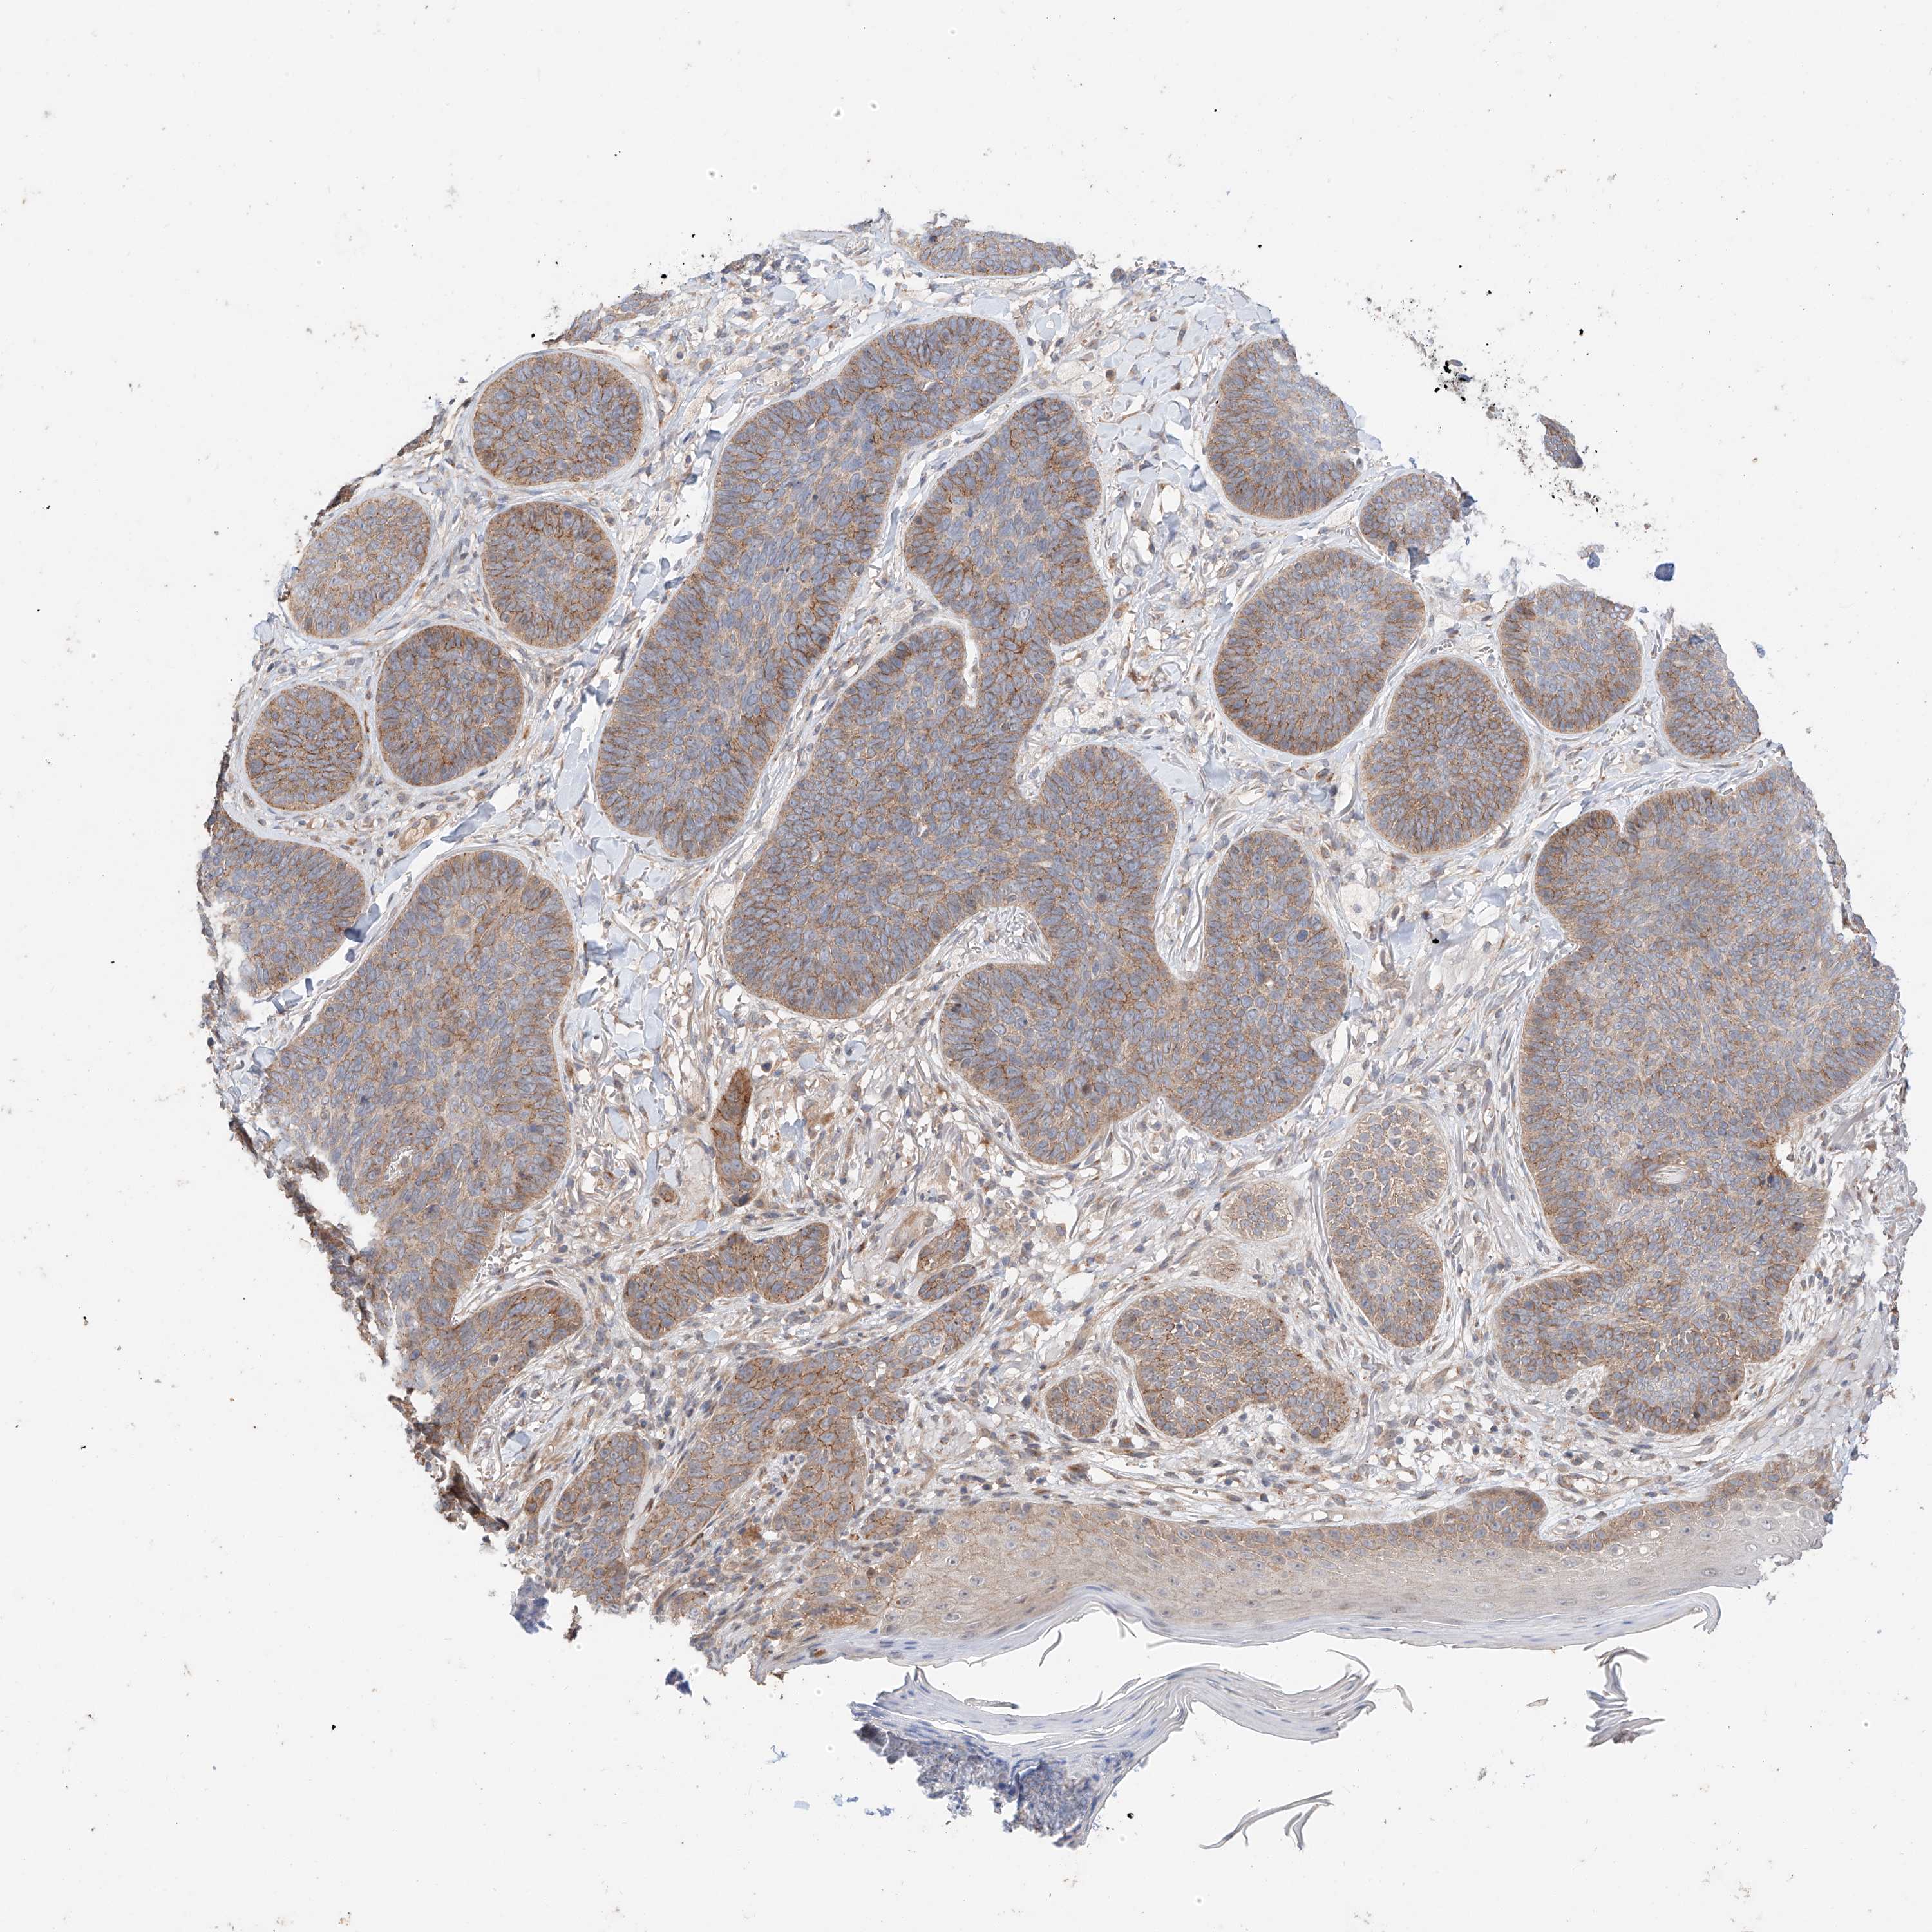

CANCER SKIN CANCER Show tissue menu

Basal cell and squamous cell cancer

SKIN CANCER - Protein expressioni

A mouse-over function shows sample information and annotation data. Click on an image to view it in a full screen mode. Samples can be filtered based on level of antibody staining by selecting one or several of the following categories: high, medium, low and not detected. The assay and annotation is described here.

Each image is clickable and will lead to virtual microscopy that enables deeper exploration of all samples and also displays staining intensity scores, fraction scores and subcellular localization as well as patient and tissue information for each sample.

Squamous cell carcinoma, metastatic, NOS